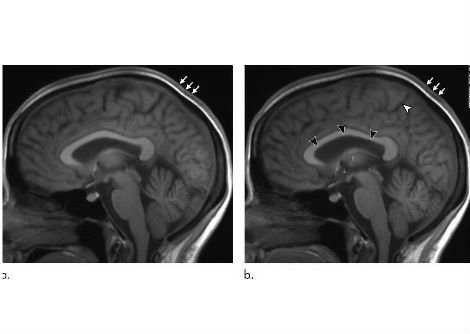

أهداف إسقاط الدماغ من الخلايا العصبية Chx10-PPN.

تم العثور على الخلايا العصبية التي تم تحفيزها من قبل الباحثين في الدماغ المتوسط في منطقة تسمى نواة Pedunculopontine (PPN) ، وهي تختلف عن الخلايا العصبية الأخرى هناك من خلال التعبير عن علامة جزيئية معينة تسمى Chx10. إن PPN شائع لجميع الفقاريات بما في ذلك البشر . لذلك على الرغم من إجراء الدراسة على الفئران ، يتوقع الباحثون أن تنطبق هذه الظاهرة على البشر أيضًا .